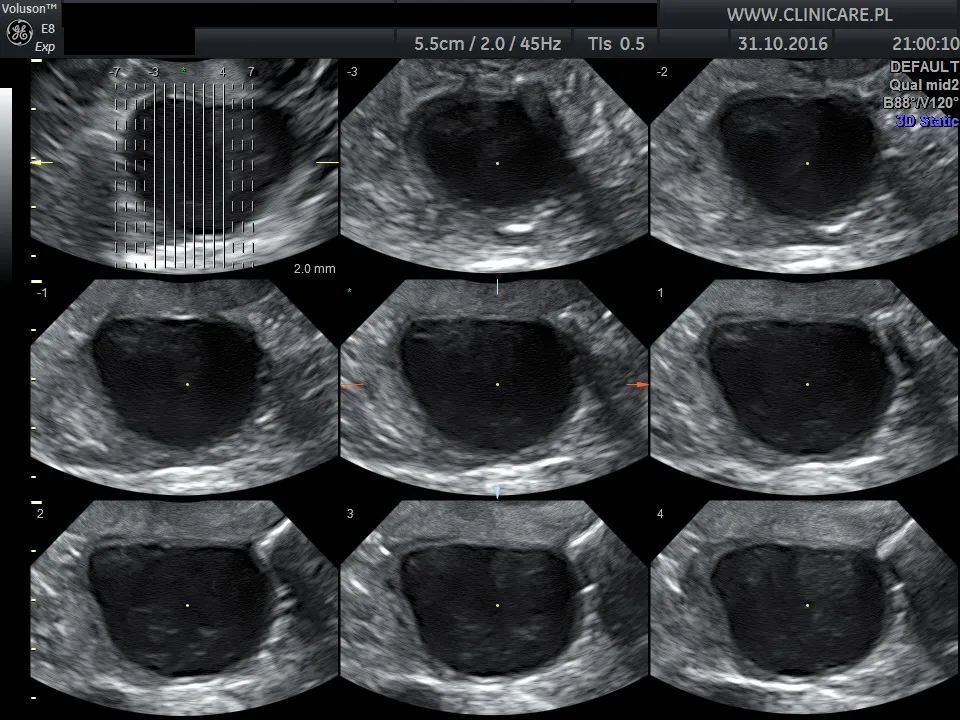

USG dopochwowe, czyli transwaginalne, to standardowy i niezwykle precyzyjny element nowoczesnej wizyty ginekologicznej. Dzięki niemu mogę zajrzeć w głąb miednicy mniejszej i uzyskać szczegółowy obraz narządów, których nie da się ocenić wzrokiem ani dotykiem. Sonda USG, wprowadzana do pochwy, emituje fale ultradźwiękowe, tworząc na monitorze dynamiczny obraz.

- Macica: Widzę jej budowę, położenie (przodo- lub tyłozgięcie), wielkość, kształt oraz ewentualne wady anatomiczne, które mogą mieć wpływ na płodność czy przebieg ciąży.

- Endometrium (błona śluzowa macicy): Mierzę jego grubość, która zmienia się w zależności od fazy cyklu, i oceniam jego jednorodność. Nieprawidłowości, takie jak polipy, przerosty czy zmiany nowotworowe, są często widoczne właśnie na tym etapie.

- Jajniki: Dokładnie oceniam ich wielkość, strukturę, obecność i liczbę pęcherzyków jajnikowych. USG pozwala mi wykryć torbiele, guzy oraz obraz charakterystyczny dla zespołu policystycznych jajników (PCOS). Jajowody zazwyczaj nie są widoczne, chyba że występuje w nich patologia, np. wodniak.

- Zatoka Douglasa: To przestrzeń za macicą, gdzie może gromadzić się płyn. Jego obecność bywa objawem np. pęknięcia torbieli, stanu zapalnego lub owulacji. Co więcej, USG pozwala na wczesne wykrycie ciąży (zarówno wewnątrzmacicznej, jak i pozamacicznej), co jest kluczowe dla zdrowia przyszłej mamy.